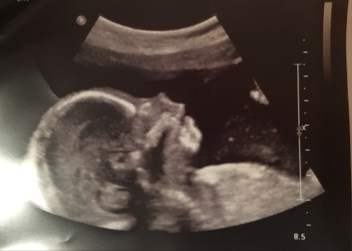

Have you or a loved been given a prenatal diagnosis?

…. or a possible diagnosis through an abnormal ultrasound scan?

Although these tests are routine and offered to women as a way of “making sure everything is ok”…. nothing prepares a pregnant woman or her partner for the news that something may be “wrong” with her baby.